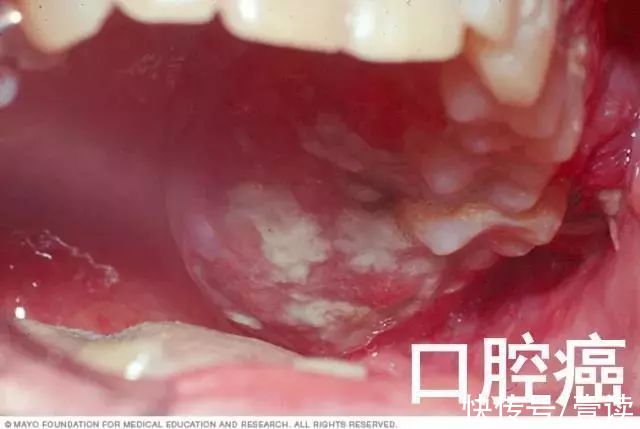

高危型HPV (HR-HPV)能诱发上皮组织恶性增生, 包括:HPV-16, -18, -31, -33, -35, -39, -45, -51, -52,-56,-58,-59,-68,-73 和 -82 计 15 种型别。高危型 HPV 感染不止与宫颈癌及癌前病变密切相关,此外还与阴道、肛门、阴唇、阴茎及口咽癌及癌前病变的发生相关。

向左滑动围观高危HPV病例(密集恐惧症患者慎滑)